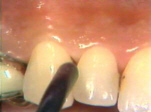

| Debajo de la

gingiva del incisivo hay cálculo subgingival observado cuando penetra

la sonda e inflamación del tejido. La gingiva también sangra fácilmente al sondear

la bolsa periodontal. |

En lingual de la mandíbula izquierda las señales de inflamación

gingival son muy prominentes. El tejido está hinchado, rojo, brillante y sangra muy fácilmente al sondear

los surcos gingivales. (Bolsas periodontales) |

En lingual de la mandíbula

derecha se encuentran los mismos signos que en la izquierda |